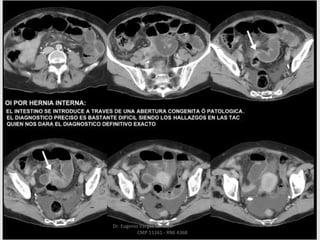

HERNIA DEL FORAMEN

DE WINSLOW

Dr. Eugenio Vargas Carbajal

CMP 11161 - RNE 4368

HERNIA DE LA

FOSITA CECAL

HERNIA TRAVES DE

ORIFICIOS

CONGENITOS DEL

EPIPLON MAYOR

HERNIA INTERNA

FOSITA DE TREITZ